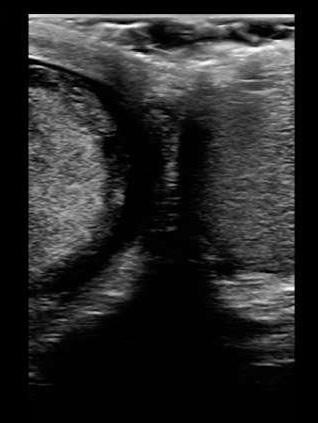

- A coronal scan showing both testicles side by side should be performed to identify differences in size and echogenicity, and vascularity. (Figure 2)

Figure 2. Also known as the ‘buddy’ or ‘spectacle’ view, a coronal scan showing both testicles side by side allows for comparison in size, relative echogenicity and blood flow.